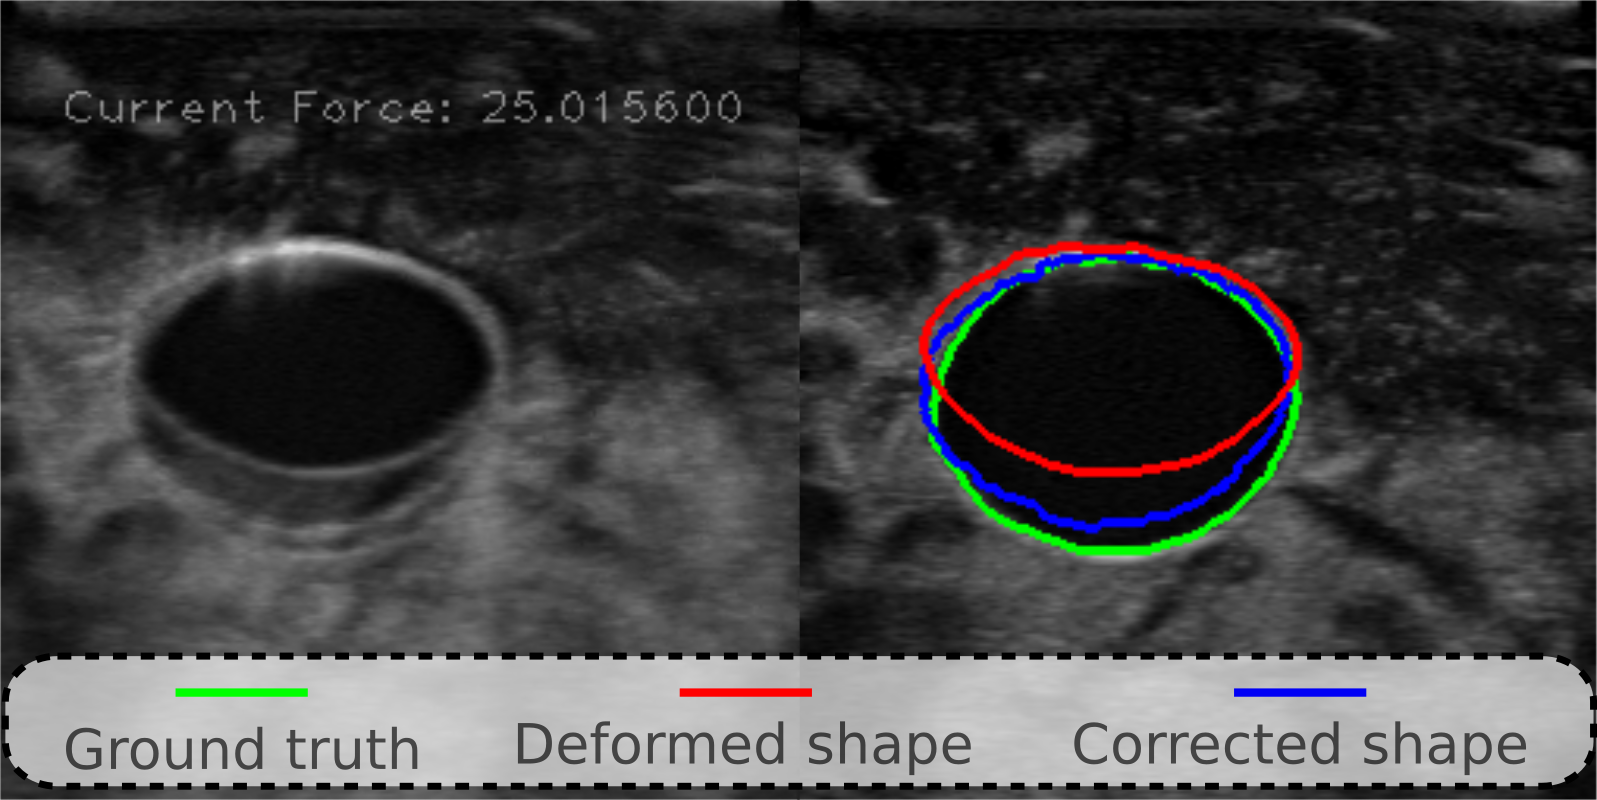

The paired images, contact forces and probe displacements recorded from the third palpation at the same position are then used for validation. To demonstrate the correction performance, the results achieved when Fc=25Nsubscript𝐹𝑐25𝑁F_{c}=25~{}N is shown in Fig. 5. The mimic artery geometry has been significantly compressed in the left view (Fig. 5). This affects measurement accuracy of the object’s geometry. Nonetheless, based on the results shown in Fig. 5, the deformed geometry (red line) can be effectively recovered to ground truth (green line). To further quantitatively analyze the result, the dice coefficient is computed and it has been improved from 0.690.690.69 to 0.920.920.92.

Refer to caption

Figure 5: Performance of the proposed deformation correction method for the 2D image obtained under 25N25𝑁25~{}N on the stiff vascular phantom. The deformed image, corrected image and the ground truth acquired when the contact force is zero are overlapped in the left plot. The right image shows the extracted blood vessel boundaries.